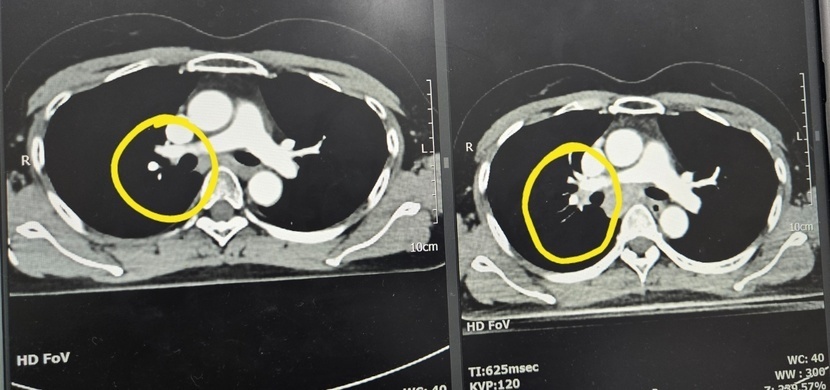

작아진 불청객